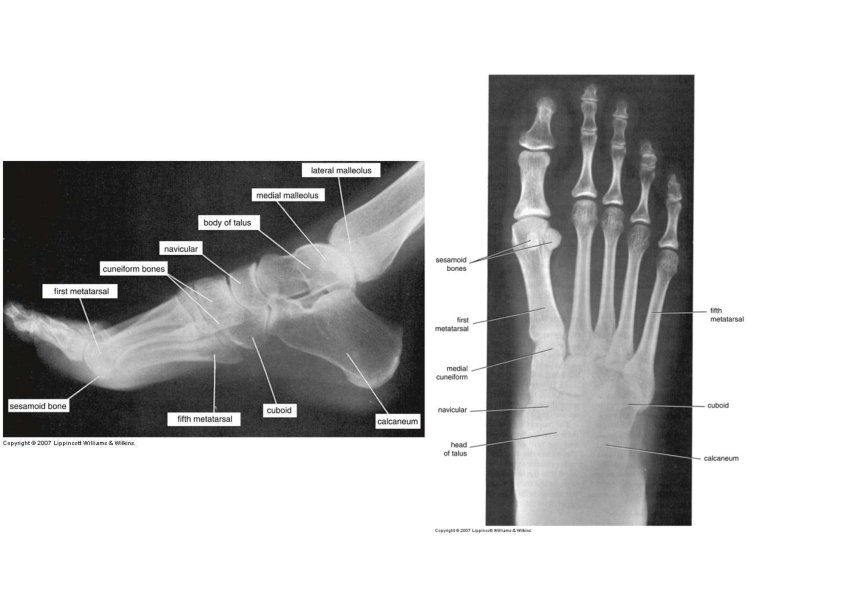

Tarsus • Proximal region of foot (contains 7 tarsal bones) • Talus = ankle bone (articulates with tibia & fibula) • Calcaneus ‐ heel bone • Cuboid, navicular & 3 cuneiforms

Tarsus • Calcaneum • • Tubercles Sustentaculum tali Sulcus calcanei Peroneal tubercle (fibular trochlea • Talus • Head, neck, and body • Sulcus tali • Sinus tarsi • Interosseous talocalcaneal ligament

Metatarsus and Phalanges • Metatarsus • 5 metatarsals (1 is most medial) • each with base, shaft and head • Phalanges • distal portion of the foot • similar in number and arrangement to the hand • big toe is hallux

Surface Anatomy of Bones of Foot • Medial tubercle of calcaneus • Medial side • Head of talus • Sustentaculum tali • Lateral side • Fibular trochlea • Tuberosity of the 5 th metatarsal